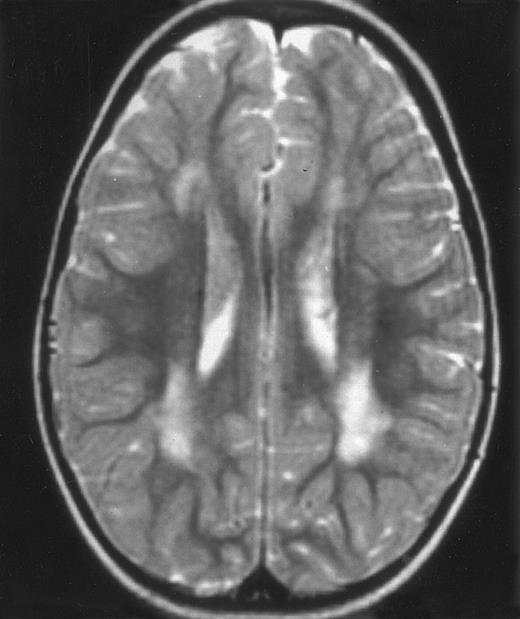

Evolution of brain lesions during HLH. (A) MRI of a 41/2-year-old girl showing focal white matter hypersignal on T2-weighted images. (B) MRI of the same child 1 year later with an important atrophy of both the white matter and the cortices.

Together, 19 patients had primary severe CNS disease progression or CNS relapse (Fig 1). Three of 19 had a CNS relapse characterized by meningitis only. Neurological symptoms occurred in 16 of these 19 patients (9 from the onset and 7 after the initial meningitis) (Fig 1). No clinical or neuroradiological difference was detected between the patients who developed neurological symptoms as the initial CNS manifestation or after initial meningitis (Table 1). The occurrence of these neurological manifestations marked a turning point in the evolution of the disease, as chemotherapy led to an improvement of the neurological symptoms in only three patients despite the use of intensive treatment by MTX IT. In these three patients, neurological sequelae persisted after the first symptoms and a relapse occurred within 3 to 10 months. Brain imaging was repeated during chemotherapy for four patients with progression of the CNS disease: in three patients, a severe brain atrophy developed (Fig 3A and B) and in the last patient who initially had contrast enhancement in cerebellar white matter, a cerebellum parenchymal loss was observed (Fig 2C). All of these 19 patients treated by chemotherapy only (n = 15) died during a last episode of coma and brain stem symptoms associated with a systemic hemophagocytic syndrome, 6 ± 6 months after the first neurological symptom (irrespective of the age at this first event). Four of these 19 patients were transplanted (one patient received an HLA-identical BMT, three an HLA-partially identical BMT). Median delay between diagnosis and BMT was 14 months (range, 2 to 20 months). All of these four patients died of BMT-related toxicity and/or disease progression.

Abnormalities on brain imaging appeared to roughly parallel the severity of clinical manifestations. All patients with neurological symptoms, but also half of the patients with initial meningitis, had abnormal brain imaging usually consisting of a combination of diffuse white matter abnormalities and necrotic areas with parenchymal volume loss, as previously described.8,23 In patients with isolated meningitis, however, only white matter abnormalities were detected, whereas necrotic lesions and cerebral atrophy were found in patients with neurological symptoms. These lesions progressed despite chemotherapy. Previous neuropathological studies have demonstrated infiltration by monocytes and activated lymphocytes of leptomeninges and brain parenchyma along penetrating vessels.24,25 Infiltration is associated with focal and confluent areas of myelin pallor, as well as neuronal loss, tissue necrosis, and cavitation,24,25 findings that were also demonstrated in the neuropathologic study of five patients in our series. Leukocytes infiltrating the CNS probably secrete cytokines and other neurotoxic factors, such as tumor necrosis factor-α (TNF-α), which may be responsible for the myelinic alteration observed in neurologically asymptomatic patients. Infiltrating leukocytes could also activate in parallel the numerous resident brain macrophages (the microglial cells) and astrocytes, which in turn, can secrete neurotoxic glutamate and free radicals.26